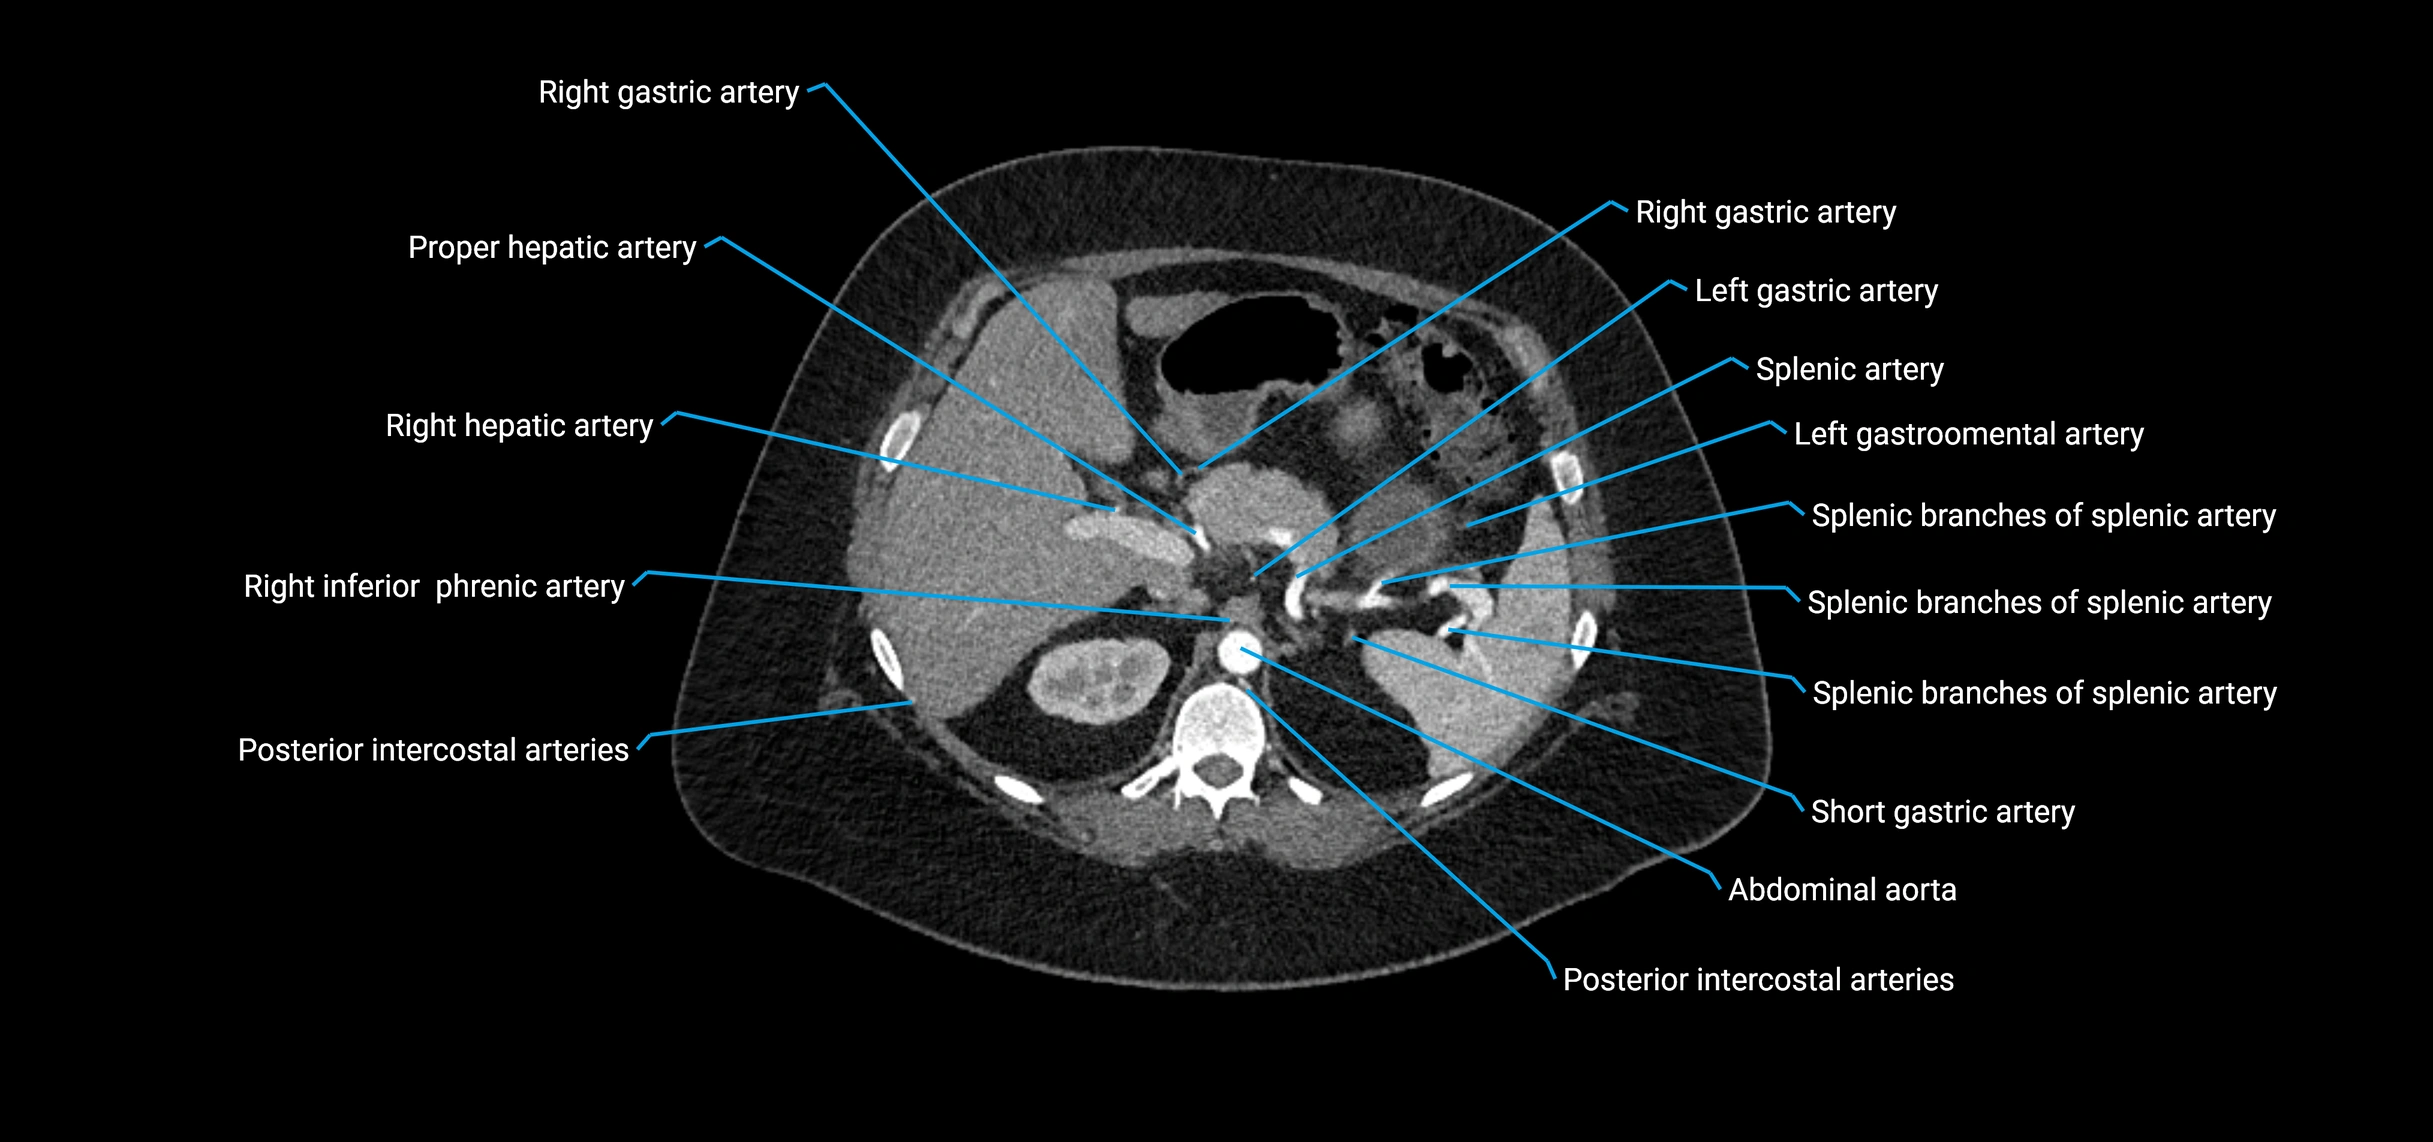

Contrast-enhanced CT (CTA):

• Gold standard for abdominal aortic imaging

• Provides excellent detail of lumen, wall, aneurysm, thrombus, and branch vessels

• Multiplanar and 3D reconstructions help in aneurysm measurement, stent graft planning, and dissection evaluation